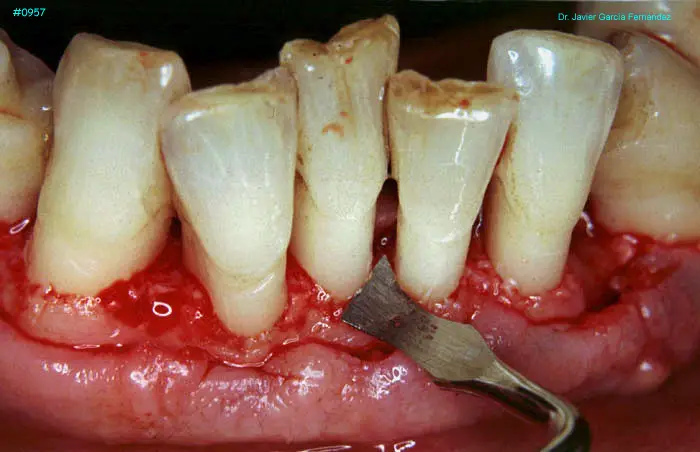

Atlas of Surgical Techniques in Periodontics. Chapter III. Atlas de Técnicas Quirúrgicas en Periodoncia